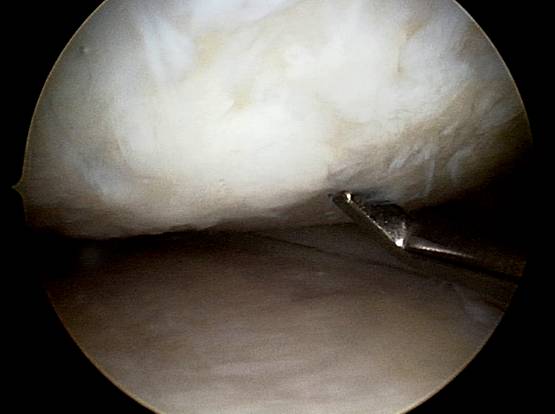

Arthroskopische Microfracturierung

Wie läuft die Operation ab?

Bei gut abgegrenzten Knorpelschaden bis zur 2,5 cm2 Grösse wird im Rahmen einer ambulanten arthroskopischen Operation der frei liegender harter Knochen auf dem Boden des Knorpeldefektes an mehreren Stellen perforiert ( " eingebrochen " = fracture ). Aus diesen Öffnungen kommt es zur Einblutung des Knorpeldefektes und aus dem Blutgerinsel ( Koagel ) entsteht innerhalb von 6-10 Wochen ein Knorpelregenerat ( "Knorpelnarbe") Die OP Dauer beträgt in Spinalanästhesie 15-30 Minuten.

Knorpel-Knochen Übertragung ( OATS, "Mosaikplastik")

Wie läuft die Operation ab ?

Dieser knorpelwiederherstellender Eingriff wird bei geeignetem isolierten, eher kleineren Knorpelschaden entweder arthroskopisch oder "mini open" unter stationären Bedingungen durchgeführt. Es werden dabei aus einem minimal belasteten Areal des betroffenen Kniegelenkes ein oder mehrere Knorpel-Knochen Zylinder entnommen und diese dann in " press fit " Technik in den speziell vorbereiteten Knorpeldefekt in der Belastungszone übertragen. Die Einheilung ist im wesentlichen in 6-8 Wochen abgeschlossen ( Knochen - Knochen Heilung ) und in dem Defekt befindet sich ein original Gelenkknorpel. Die Entnahmestellen füllen sich mit Faserknorpelgewebe.